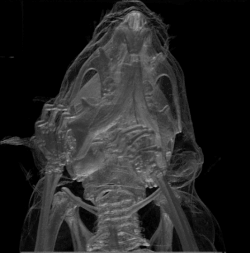

عِلمُ التَّشريح هو أحد فروع علم الأحياء، يُعنى بدراسة شكل وبنية الكائنات الحية وكذا أجزائها (أعضاء، أنسجة).[1] يرتبط علم التشريح بطبيعته بعلم الأجنة، والتشريح المُقَارَن، وعلم الأحياء التطوُّري،[2] لأنه ومن خلال العمليات التي تَدرُسُها هذه العلوم، ينشأ التشريح في إطار زمني فوري (علم الأجنة)، وعلى المدى الطويل (التطور). يُعتبر علم التشريح البشري بأحد العلوم الطبية الأساسية.[مبهم][3] ينقسم التشريح إلى تشريح عياني ومجهري. يُعنى علم التشريح العياني بفحص أجزاء جسم الحيوان باستخدام البصر. يتضمن التشريح العياني فرع التشريح السطحي. بينما يتضمّن التشريح المجهري استخدام أدوات بصريّة في دراسة أنسجة البُنى المختلفة، ويُعرف كذلك باسم علم الأنسجة، ويتضمن أيضاً دراسة الخلايا. اتّسم التشريح بالفهم التدريجي لوظائف أعضاء وبُنى الجسم البشري. وقد حسّنت الطرق في دراسة التشريح بشكل كبير، بدءاً من فحص الحيوانات، عبر تشريح جثثها وجِيَفِها، حتى وصلت لاستخدام تقنيات التصوير الطبية في القرن العشرين، بما في ذلك الأشعة السينية، والموجات فوق الصوتية، والتصوير بالرنين المغناطيسي. شَكَّل علما التشريح ووظائف الأعضاء زوجاً من العلوم التي تدرَّس غالباً معاً في اختصاصات عديدة، حيث يُدرِّس هذان العلمان بنية الجسم ووظائفه على التوالي.